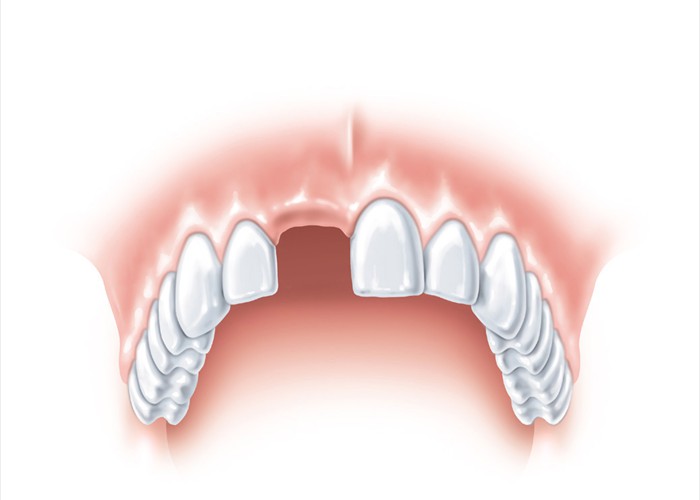

Ein fehlender oberer Frontzahn muss ersetzt werden.

Ein fehlender oberer Frontzahn muss ersetzt werden.

Für die klassische Versorgung mit einer Brücke müssen die Nachbarzähne beschliffen werden. Bei gesunden Nachbarzähnen sollte man dies unbedingt vermeiden.

Für die klassische Versorgung mit einer Brücke müssen die Nachbarzähne beschliffen werden. Bei gesunden Nachbarzähnen sollte man dies unbedingt vermeiden.